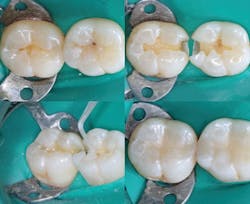

Resin-based composite

What is the obvious conclusion? Resin-based composite restorations are not sealed, and the tooth preparations contain billions of organisms that must be killed before placing restorations. If this is not done, subsequent caries (usually called recurrent caries) is really continuing caries. Kill the organisms. Additionally, use conventional glass ionomer as a dentin substitute in deep preparations and where cariostatic activity is needed.